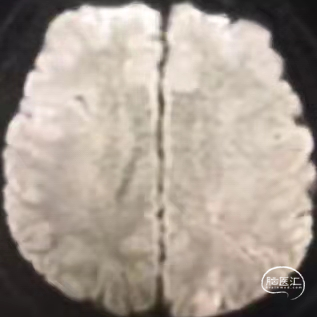

作者认为:术前评估核心梗塞仍很重要,病人不同代偿不同,对缺血耐受也不同。DWI影像可评估核心梗死区。

1. 梗死灶出现与术前DWI影像一致

2. 鞍上池及环池清晰

3. 左额顶叶皮层及半卵圆中心区没有梗塞

术后十天复查头部CT影像